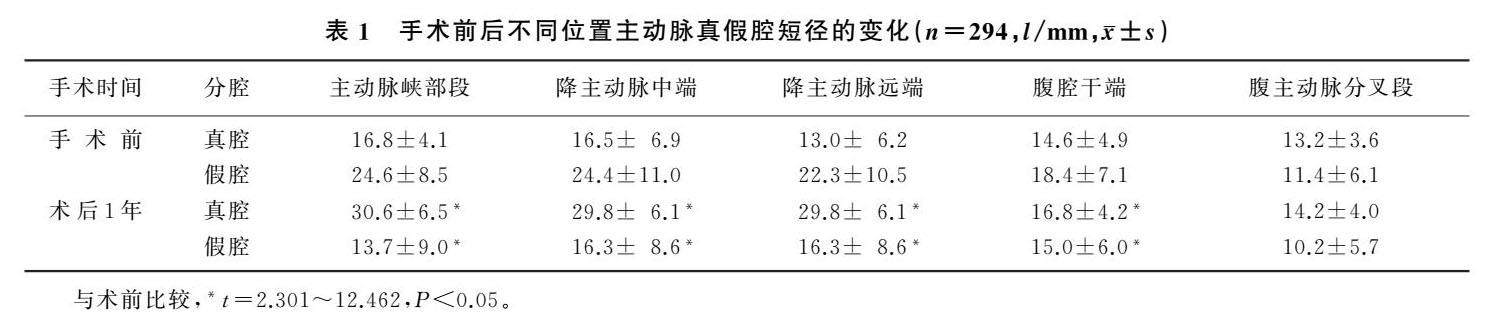

论著 | 覆膜支架腔内隔绝术对高海拔地区B型主动脉夹层疗效及预后因素

论著 | 覆膜支架腔内隔绝术对高海拔地区B型主动脉夹层疗效及预后因素